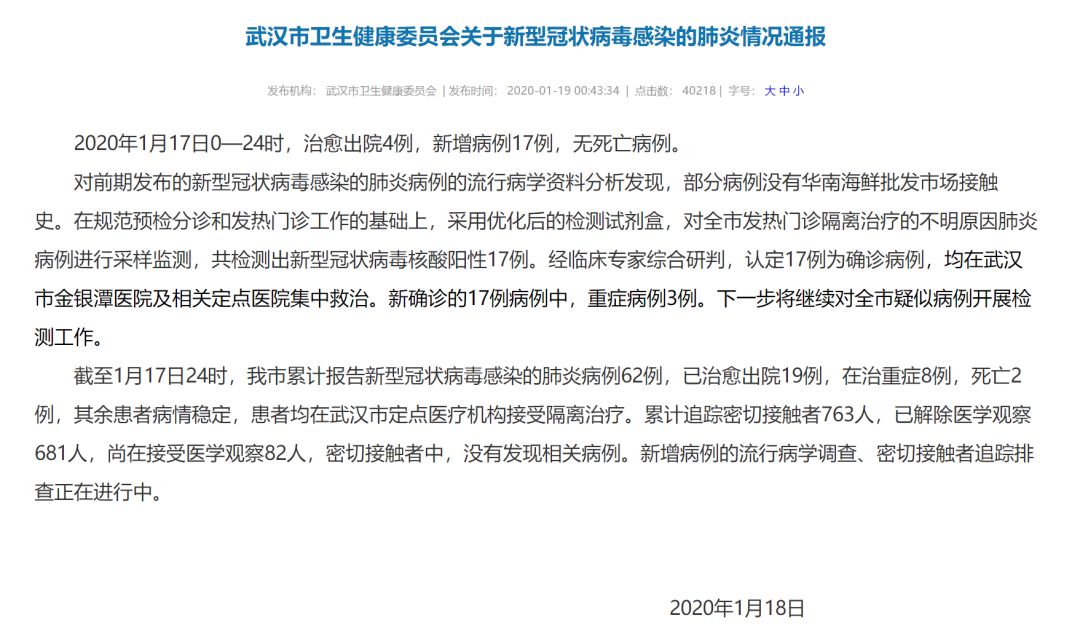

截至1月17日24时,武汉市累计报告新型冠状病毒感染的肺炎病例62例,已治愈出院19例,在治重症8例,死亡2例,其余患者病情稳定,患者均在武汉市定点医疗机构接受隔离治疗。累计追踪密切接触者763人,已解除医学观察681人,尚在接受医学观察82人。